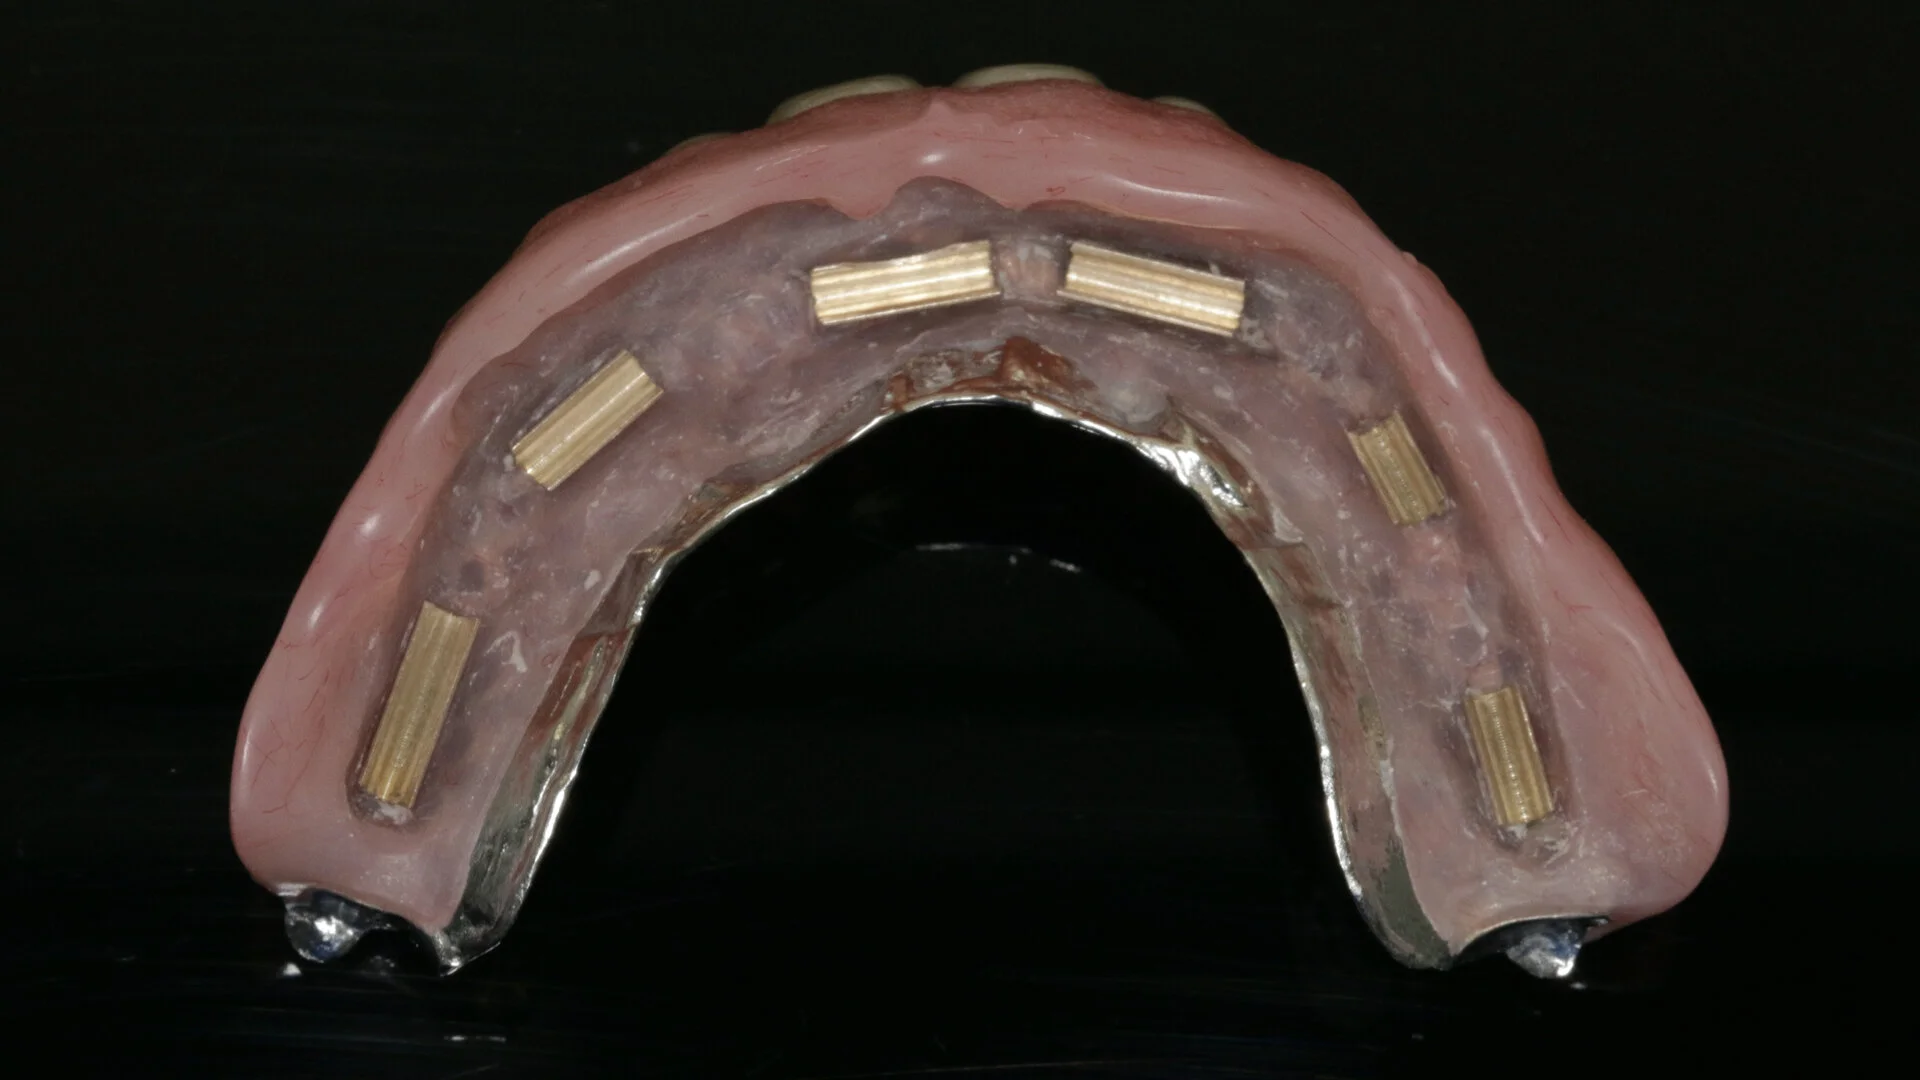

• Bar design

• Attachment choice and design

• Mucosal- and implant-borne removable prostheses